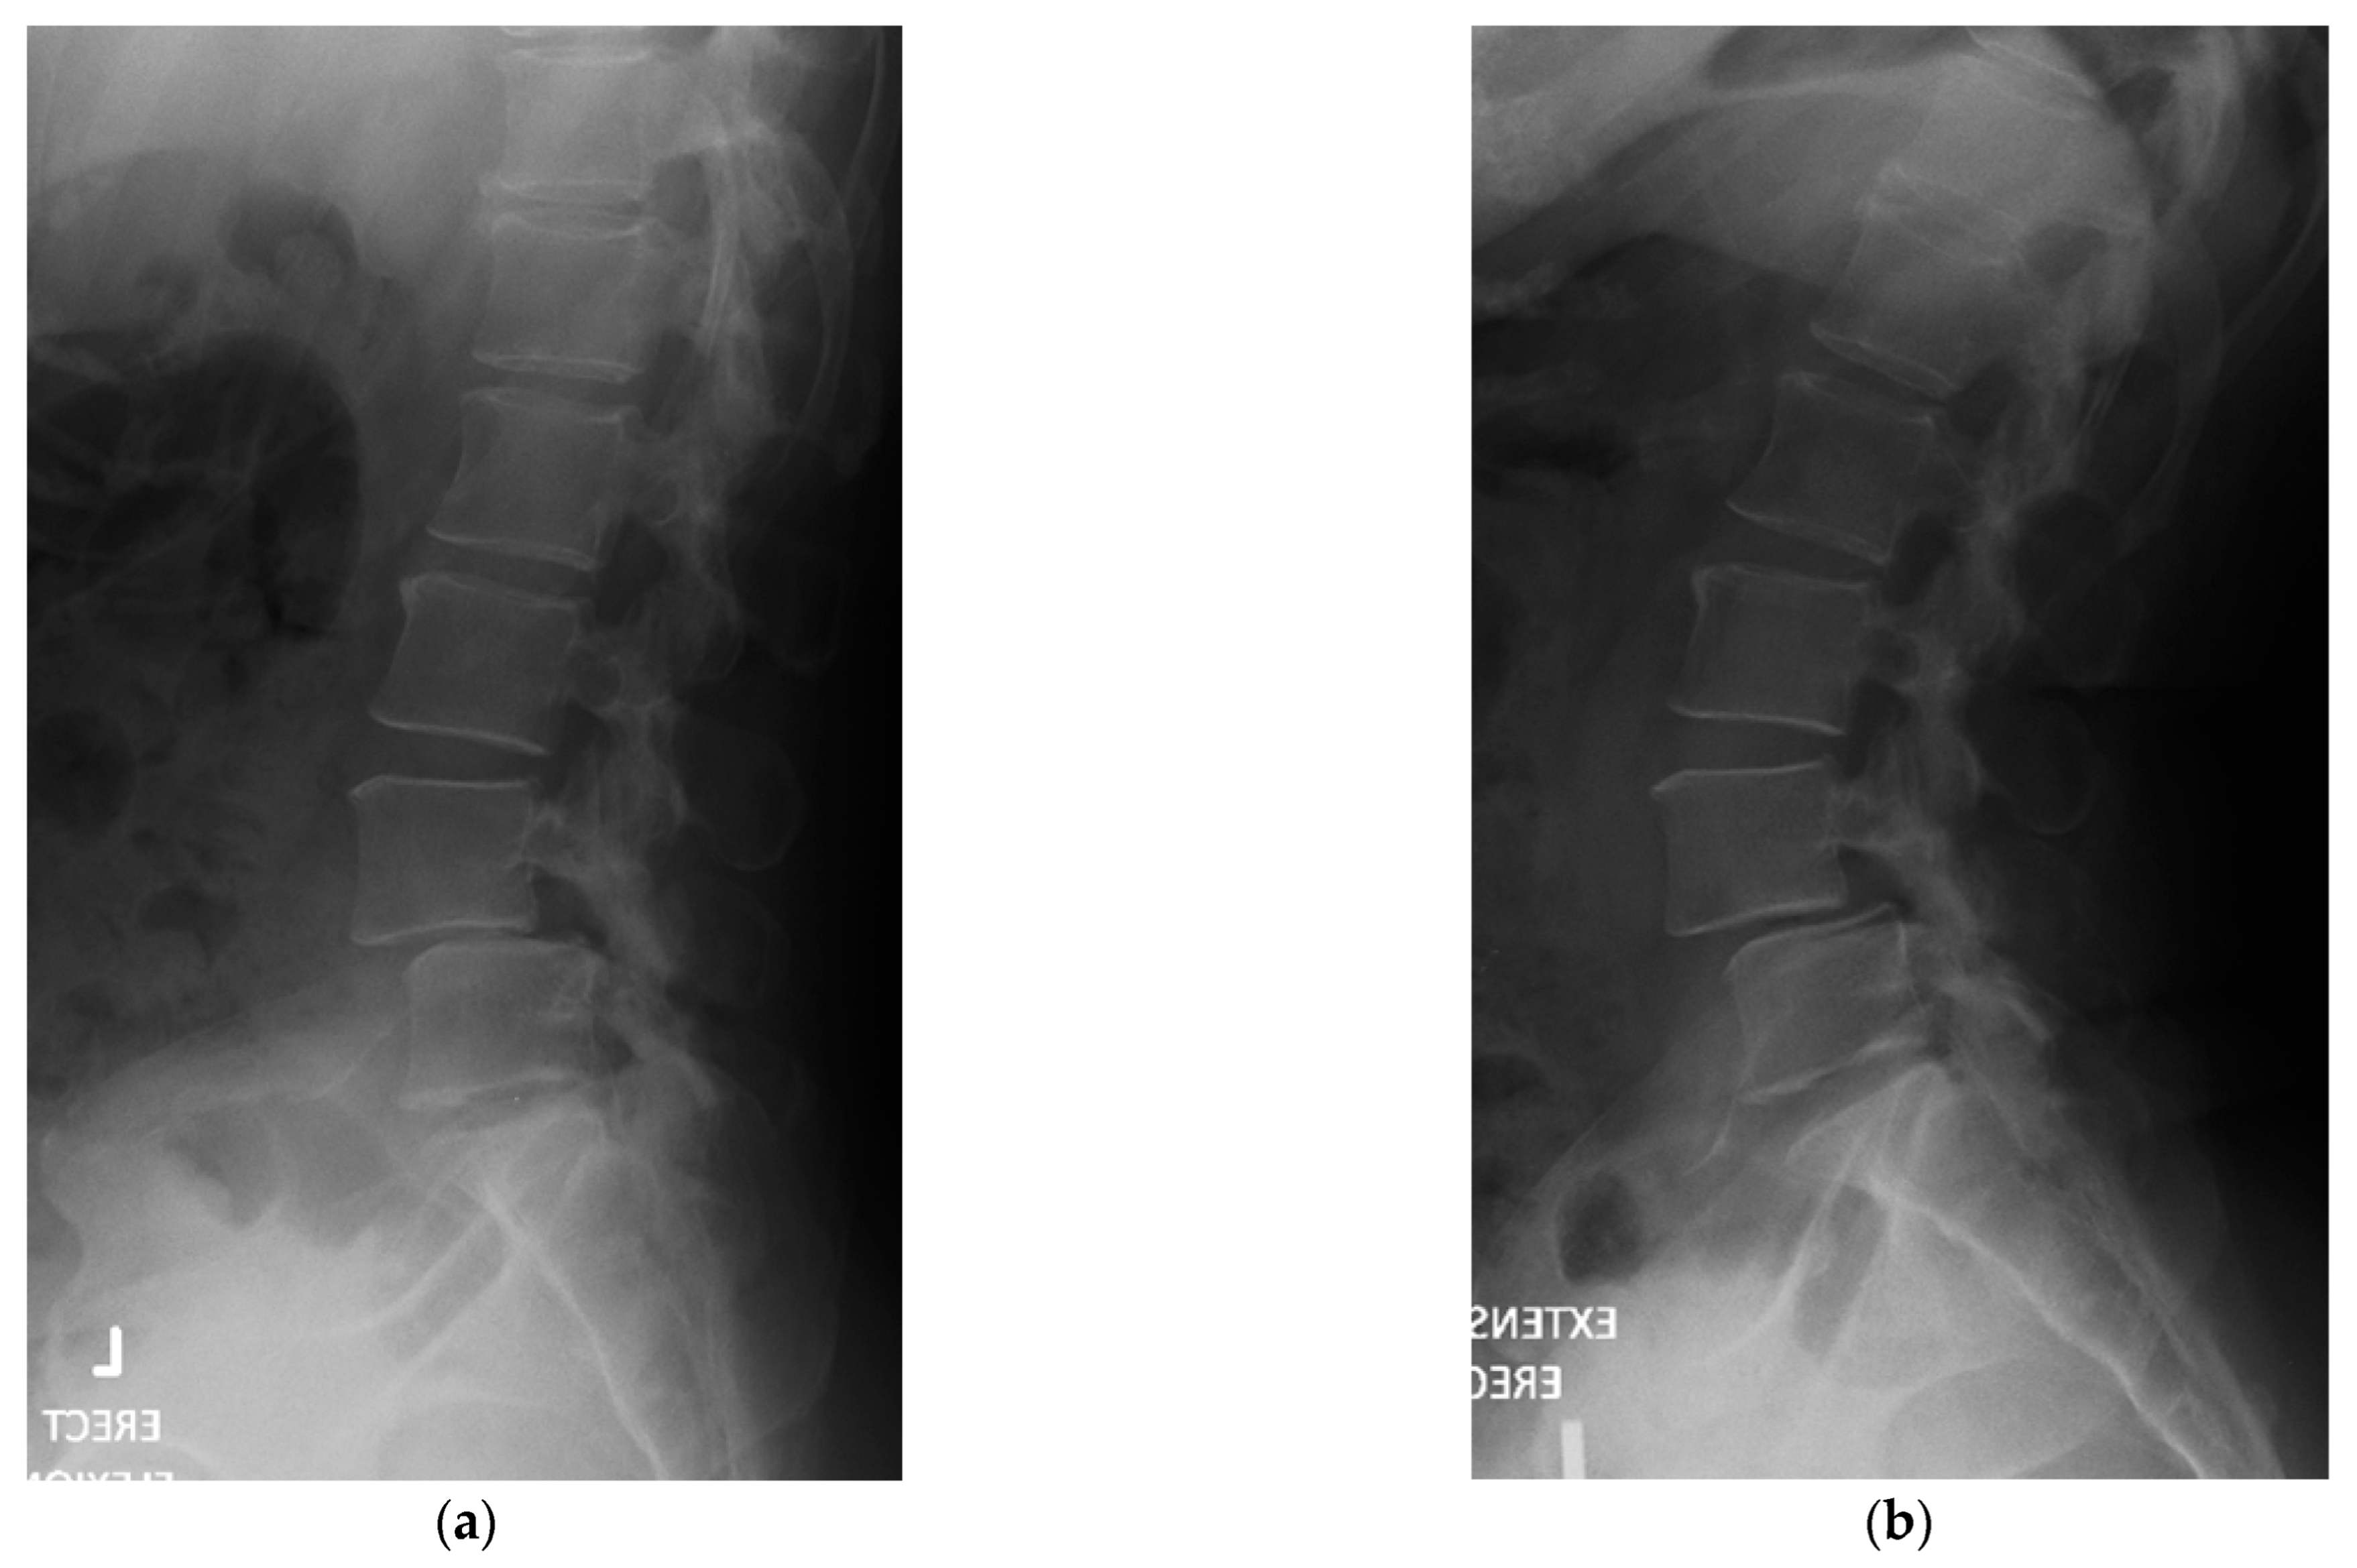

4.1. Case 1: Madam M

4.2. Case 2: Madam R

4.3. Case 3: Madam M